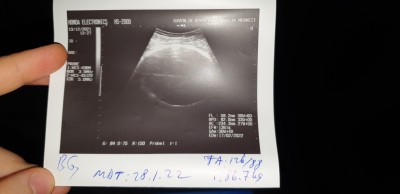

kızlar bugün doktora gittim doğru düzgün bir şey söylemedi anlayanınız var mı? Ayrıca kilosu haftama göre az gibi geldi sizce de öyle mi?

33+5

Fl yazan yeri 7 ile çarpın boyu öyle bulunuyor

Fl yazan yer 59.2 yazıyor

41.5 santimmiş bebeğin

Tr için 33.hafta boy kilo standartı 44 santim/ 1920 gram

1.361 kilo

1.361 mi 2.361 mi 33 haftaya 1.361 az bence sağlıklı olsunda

1.500 bile değil sanırım o bile az bu haftaya göre buradaki doktorlardan nefret ediyorum ya doğru düzgün ilgileniyorlar bir şey söylemiyorlar